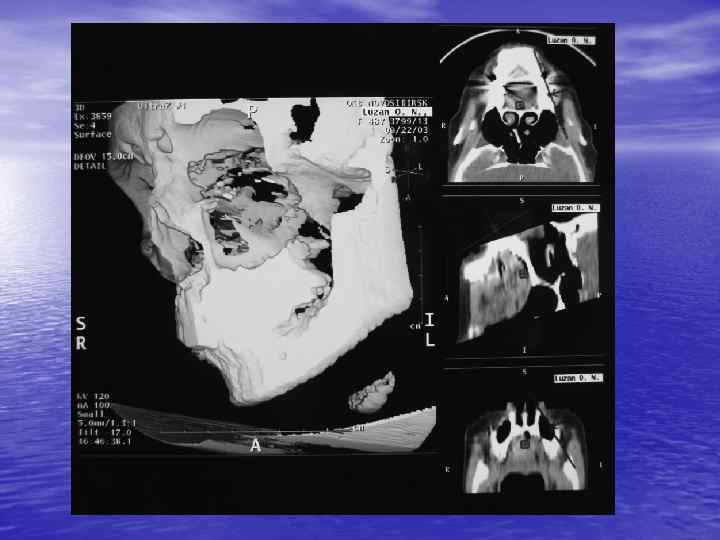

Анализ изображения: üструктурный (анатомический) - оценка морфологии üденситометрический - оценка плотности ткани

Преимущества спиральной КТ: ü Возможность проведения исследования с болюсным ü ü ü ü ü контрастированием Высокая разрешающая способность; Высокая скорость исследования; Получение высококачественных изображений костных структур; Возможность обследования всего тела; Возможность проведения исследования больных под наркозом; Возможность детальной оценки состояния крупных и периферических сосудов в условиях искусственного контрастирования; Высокая информативность метода при черепномозговых травмах в остром периоде; Ранняя диагностика ишемических и геморрагических инсультов; Метод выбора для диагностики заболеваний легких; Планирование лучевой терапии.